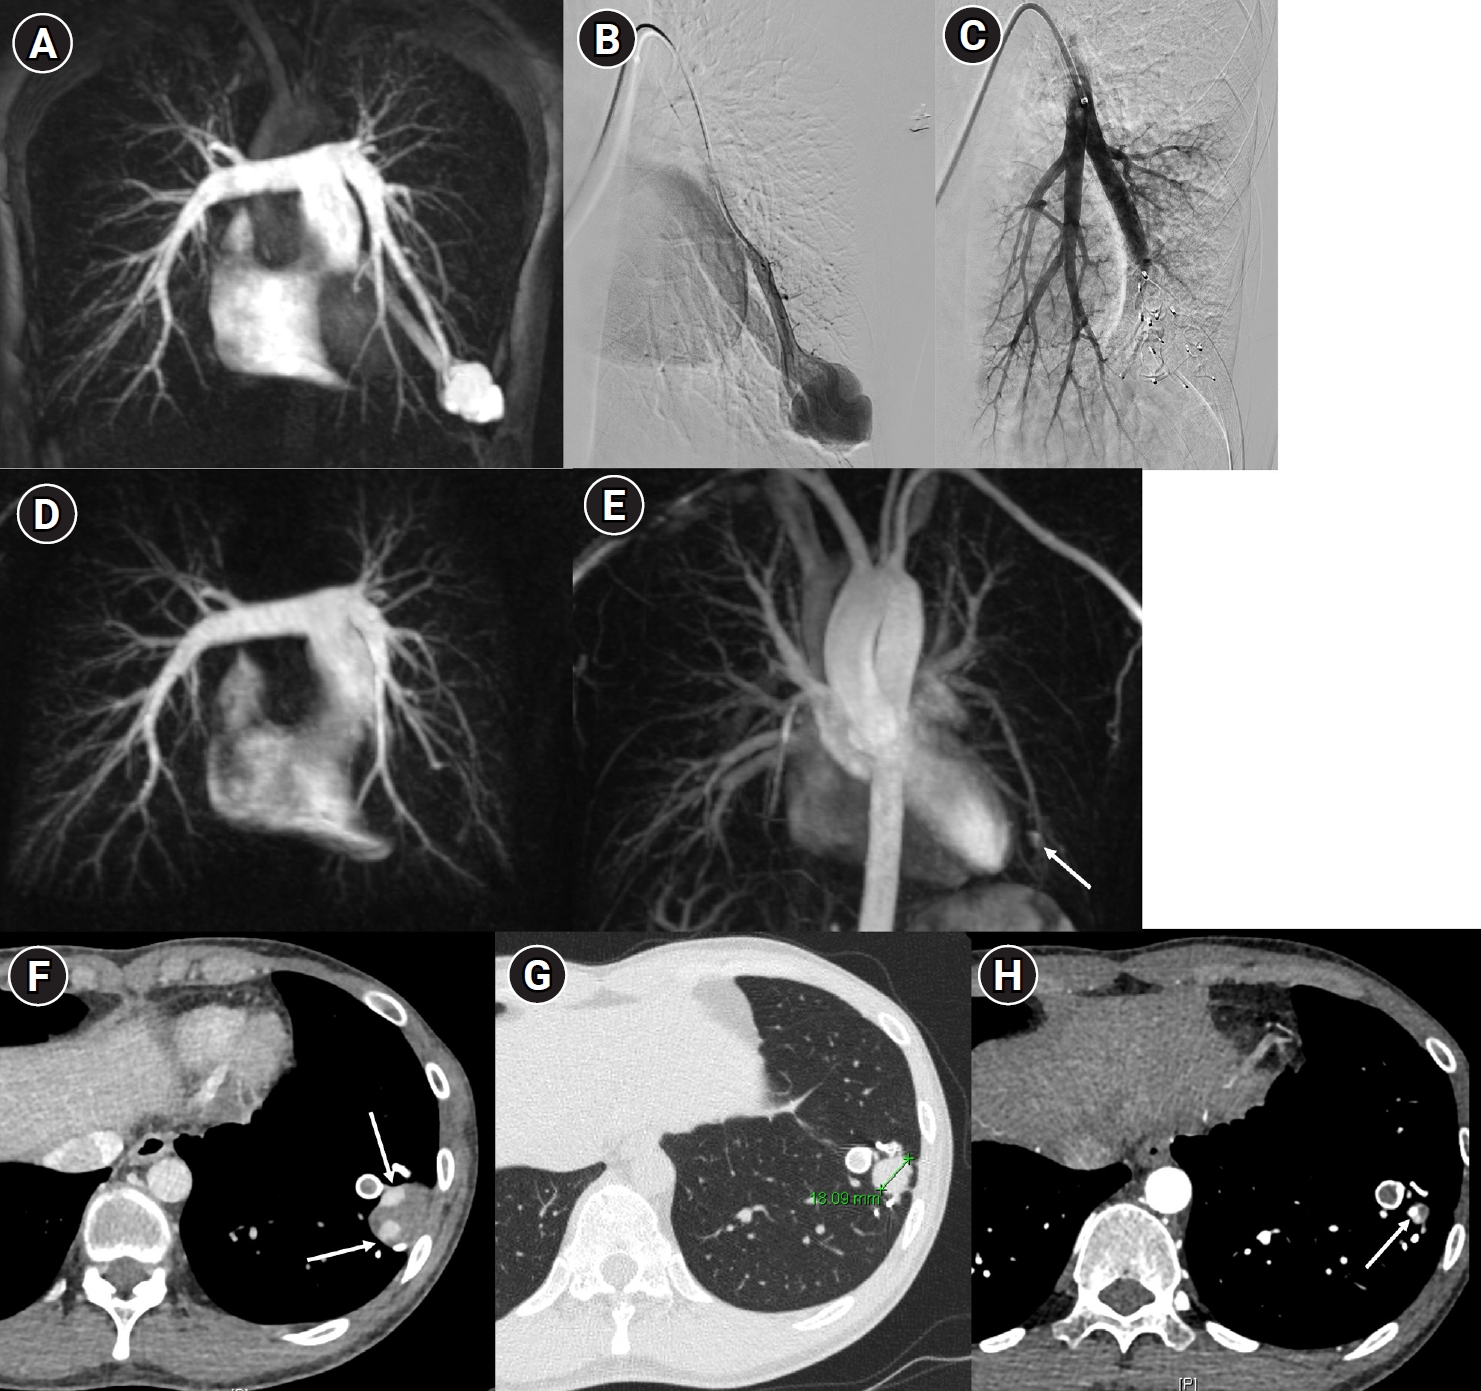

Fig. 5.

Embolization procedure in a patient with a feeding artery diameter of 2.6 mm and a venous sac diameter of 8 mm in the right lower lobe. (A) Selective angiography of the right lower lobe pulmonary arteriovenous malformation. (B) A 7 mm Amplatzer vascular plug type IV (arrow) was deployed into an approximately 8 mm venous sac, and it was determined that this would not provide adequate embolization effect. (C) By repositioning the Amplatzer plug and deploying it at the distal part of the feeding artery (arrow), it becomes clear that an Amplatzer vascular plug sufficiently larger than the feeding artery’s size is needed to effectively achieve embolization.

Fig. 5. Embolization procedure in a patient with a feeding artery diameter of 2.6 mm and a venous sac diameter of 8 mm in the right lower lobe. (A) Selective angiography of the right lower lobe pulmonary arteriovenous malformation. (B) A 7 mm Amplatzer vascular plug type IV (arrow) was deployed into an approximately 8 mm venous sac, and it was determined that this would not provide adequate embolization effect. (C) By repositioning the Amplatzer plug and deploying it at the distal part of the feeding artery (arrow), it becomes clear that an Amplatzer vascular plug sufficiently larger than the feeding artery’s size is needed to effectively achieve embolization.